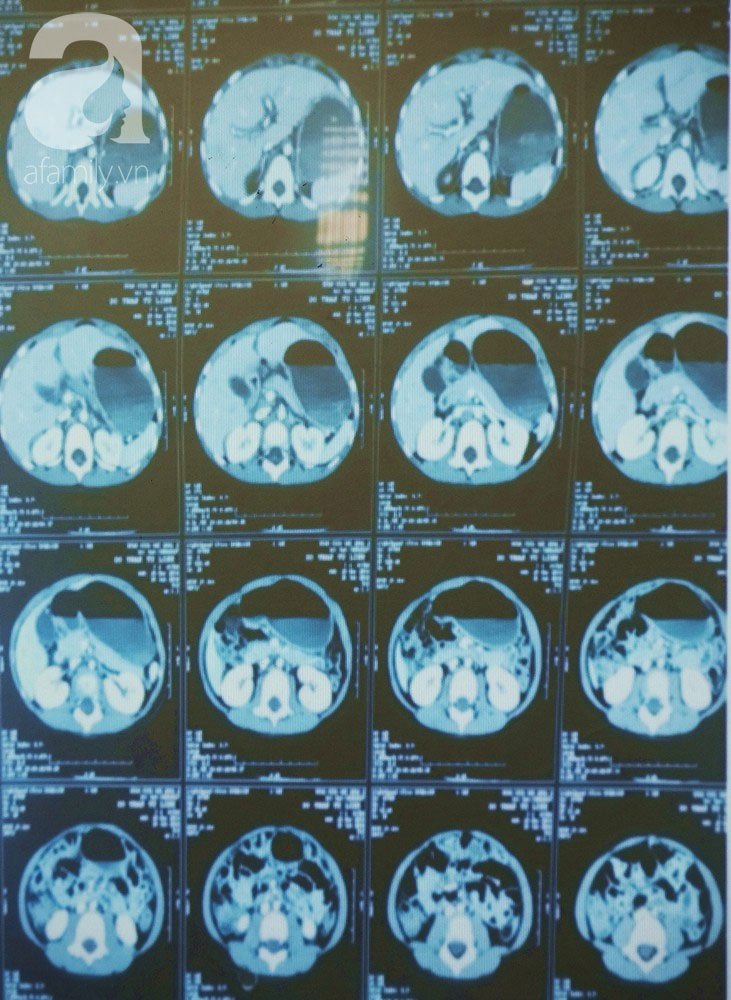

Bác sĩ Trịnh Hữu Tùng, Giám đốc BV Nhi đồng 2 cho biết vào khuya ngày 26/6, một bé gái 4 tuổi được người nhà đưa đến BV Nhi đồng 2 trong tình trạng lơ mơ, chảy nhiều máu, gãy tay, có vết thương hở ở chân, bụng trướng, tri giác không ốn định... do té từ tầng 7 một chung cư trên địa bàn TP.HCM.

Kết quả kiểm tra ban đầu cho thấy có mảu tụ dưới màng cứng và xuất huyết vùng hố sau, chấn thương dập gan, xương cánh tay trái gẫy hở độ 3, tổn thương động mạch cánh tay trái. Ê kíp trực hội chẩn khẩn cấp và quyết định xử trí phẫu thuật ngay cho bệnh nhi.

Rạng sáng 27/6, bé được đưa vào phòng mổ để kết hợp xương, vi phẫu thuật nối động mạch cánh tay trái.

Ca phẫu thuật diễn ra khẩn trương trong vòng 1 giờ. Sau dó bệnh nhi đã được đưa về Khoa hổi sức để theo dõi tiếp tục và điều trị bảo tồn các tổn thương ở vùng đầu, gan. Sau hơn 1 tuần điều trị tich cực, bé hồi tỉnh và được chuyển về khoa Ngoại thần kinh. Hiện tại, bé được bác sĩ cho xuất viện.

Các bác sĩ Khoa Ngoại thần kinh BV Nhi đồng 2 cho biết, bệnh nhi bị thương rất nặng nhưng không mất mạng ngay lập tức là do được mái che ở tầng 1 đỡ trước khi tiếp đất. Các ca tai nạn bé té lầu thấp, té gác vào cẩp cứu ở BV là thường gặp. Tuy nhiên trường hợp té từ lầu 7 xuống đất mà vẫn sống thì đây là ca đầu tiên BV tiếp nhận và điều trị.